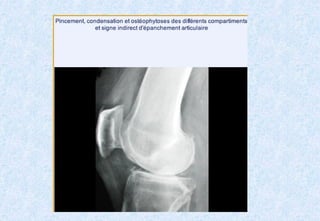

Radiographie standardRadiographie standard ::

IncidencesIncidences ::

-Face debout en extension ou en position de Schuss.Face debout en extension ou en position de Schuss.

-Profil debout en flexion.Profil debout en flexion.

RésultatsRésultats ::

-Pincement de l’interligne articulaire.Pincement de l’interligne articulaire.

-Condensation sous-chondrale du plateau tibial.Condensation sous-chondrale du plateau tibial.

-Géodes sous chondrales (rares).Géodes sous chondrales (rares).

-Ostéophytes (condyles fémoraux plateaux tibiaux, épines tibiales).Ostéophytes (condyles fémoraux plateaux tibiaux, épines tibiales).

Dans la gonarthrose évoluée :Dans la gonarthrose évoluée :

-Enfoncement cupuliforme des plateaux tibiaux.Enfoncement cupuliforme des plateaux tibiaux.

Il n’existe pas de parallélisme radio-clinique.

Arthrose fémoro-tibiale.Arthrose fémoro-tibiale. RadiographiestandardRadiographie standard :: IncidencesIncidences :: -Face debout en extension ou en position de Schuss.Face debout en extension ou en position de Schuss. -Profil debout en flexion.Profil debout en flexion. RésultatsRésultats :: -Pincement de l’interligne articulaire.Pincement de l’interligne articulaire. -Condensation sous-chondrale du plateau tibial.Condensation sous-chondrale du plateau tibial. -Géodes sous chondrales (rares).Géodes sous chondrales (rares). -Ostéophytes (condyles fémoraux plateaux tibiaux, épines tibiales).Ostéophytes (condyles fémoraux plateaux tibiaux, épines tibiales). Dans la gonarthrose évoluée :Dans la gonarthrose évoluée : -Enfoncement cupuliforme des plateaux tibiaux.Enfoncement cupuliforme des plateaux tibiaux. Il n’existe pas de parallélisme radio-clinique.